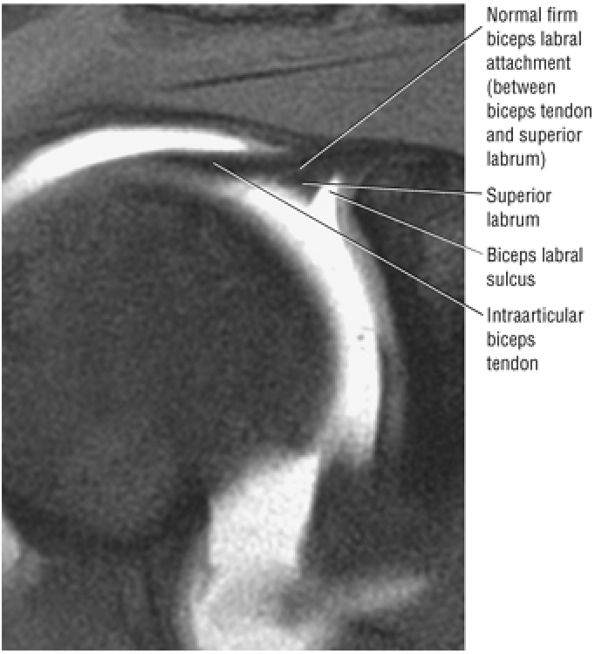

The BLC is classified as type 1, 2, or 3.

Type 1 BLC has the superior labrum firmly attached to the superior pole of the glenoid.

The superior labral sulcus in BLC types 2 and 3 should not be mistaken for the more anterior (anterosuperior quadrant) sublabral foramen (also known as the sublabral hole).

Type 1 BLC (see Fig. 8.74A; Fig. 8.75): The BLC is firmly adherent to the superior pole of the glenoid. There is no sublabral foramen in the anterosuperior quadrant. This type of BLC attachment corresponds to the morphology of the BLC in the posterior wedge or type B labrum.

Type 2 BCL (see Fig. 8.74B; Fig. 8.76): The BLC is attached several millimeters medial to the sagittal plane of the glenoid. The superior pole of the glenoid continues its hyaline cartilage surface under the labrum. This configuration has a small sulcus at the superior pole of the glenoid that may be continuous with the more anterior variation of a sublabral foramen and communicate with the subscapularis bursa.60 This type of BLC

attachment, with a triangular superior labrum and a free central edge, is associated with both the superior wedge labrum and the combined superior and anterior wedge labrum. -

Type 3 BLC (see Fig. 8.74C; Fig. 8.77): The labrum is very meniscoid in shape and has a large sulcus that projects under the labrum and over the cartilaginous pole of the glenoid. It is seen in the meniscal or meniscoid (type E) labrum.